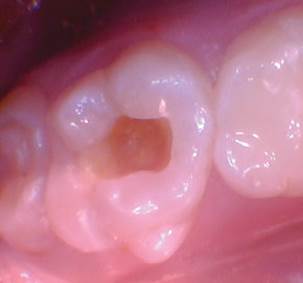

Caso 3

La caries recurrente en un diente primario que involucra múltiples superficies generalmente conduce a una cobertura total y con razón. Sabemos que los materiales a base de resina tienen fugas en ambientes hostiles ácidos y acribillados de sacarosa; por lo tanto, se recomienda una cobertura total en estos casos. ¿Qué pasaría si pudiéramos restaurar con un material más estético para los padres estéticos? En estos casos estéticos, todavía necesitamos resistencia y un material activo no inerte.

Figura 1. Fotografía preoperatoria del segundo molar primario superior derecho con caries distoocluso-bucal. En el pasado, al menos para mí, el tratamiento habría sido una corona de cobertura total (probablemente de acero inoxidable). Debido a las preocupaciones estéticas de los padres, es bueno tener una opción alternativa, especialmente un material que sea activo dentro del entorno oral. |

Figura 2. La caries se excavó y se eliminó todo el esmalte socavado. |